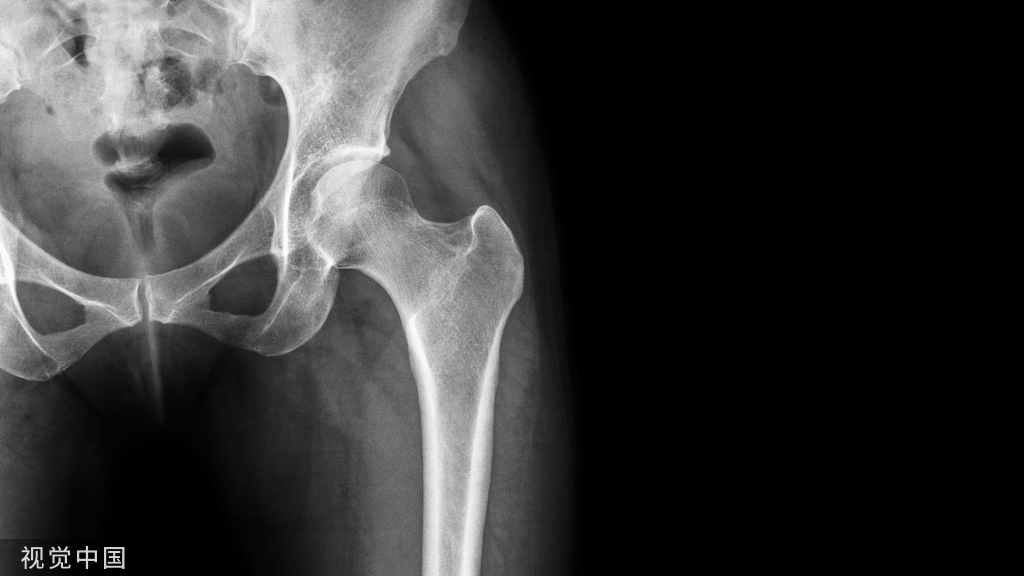

影像检查

• 骨盆的前后位X线平片可以与对侧比较(对于发生在股骨转子间或股骨颈基底部的复杂股骨近端骨折特别有用)。

• 包括髋关节和膝关节在内,股骨全长前后位和侧位X线平片是必需的。

• 极少数情况下,CT有助于准确的确定转子下区域的骨折类型。例如,对于累及梨状肌隐窝的骨折,髓内钉的操作就需要特殊的技术。